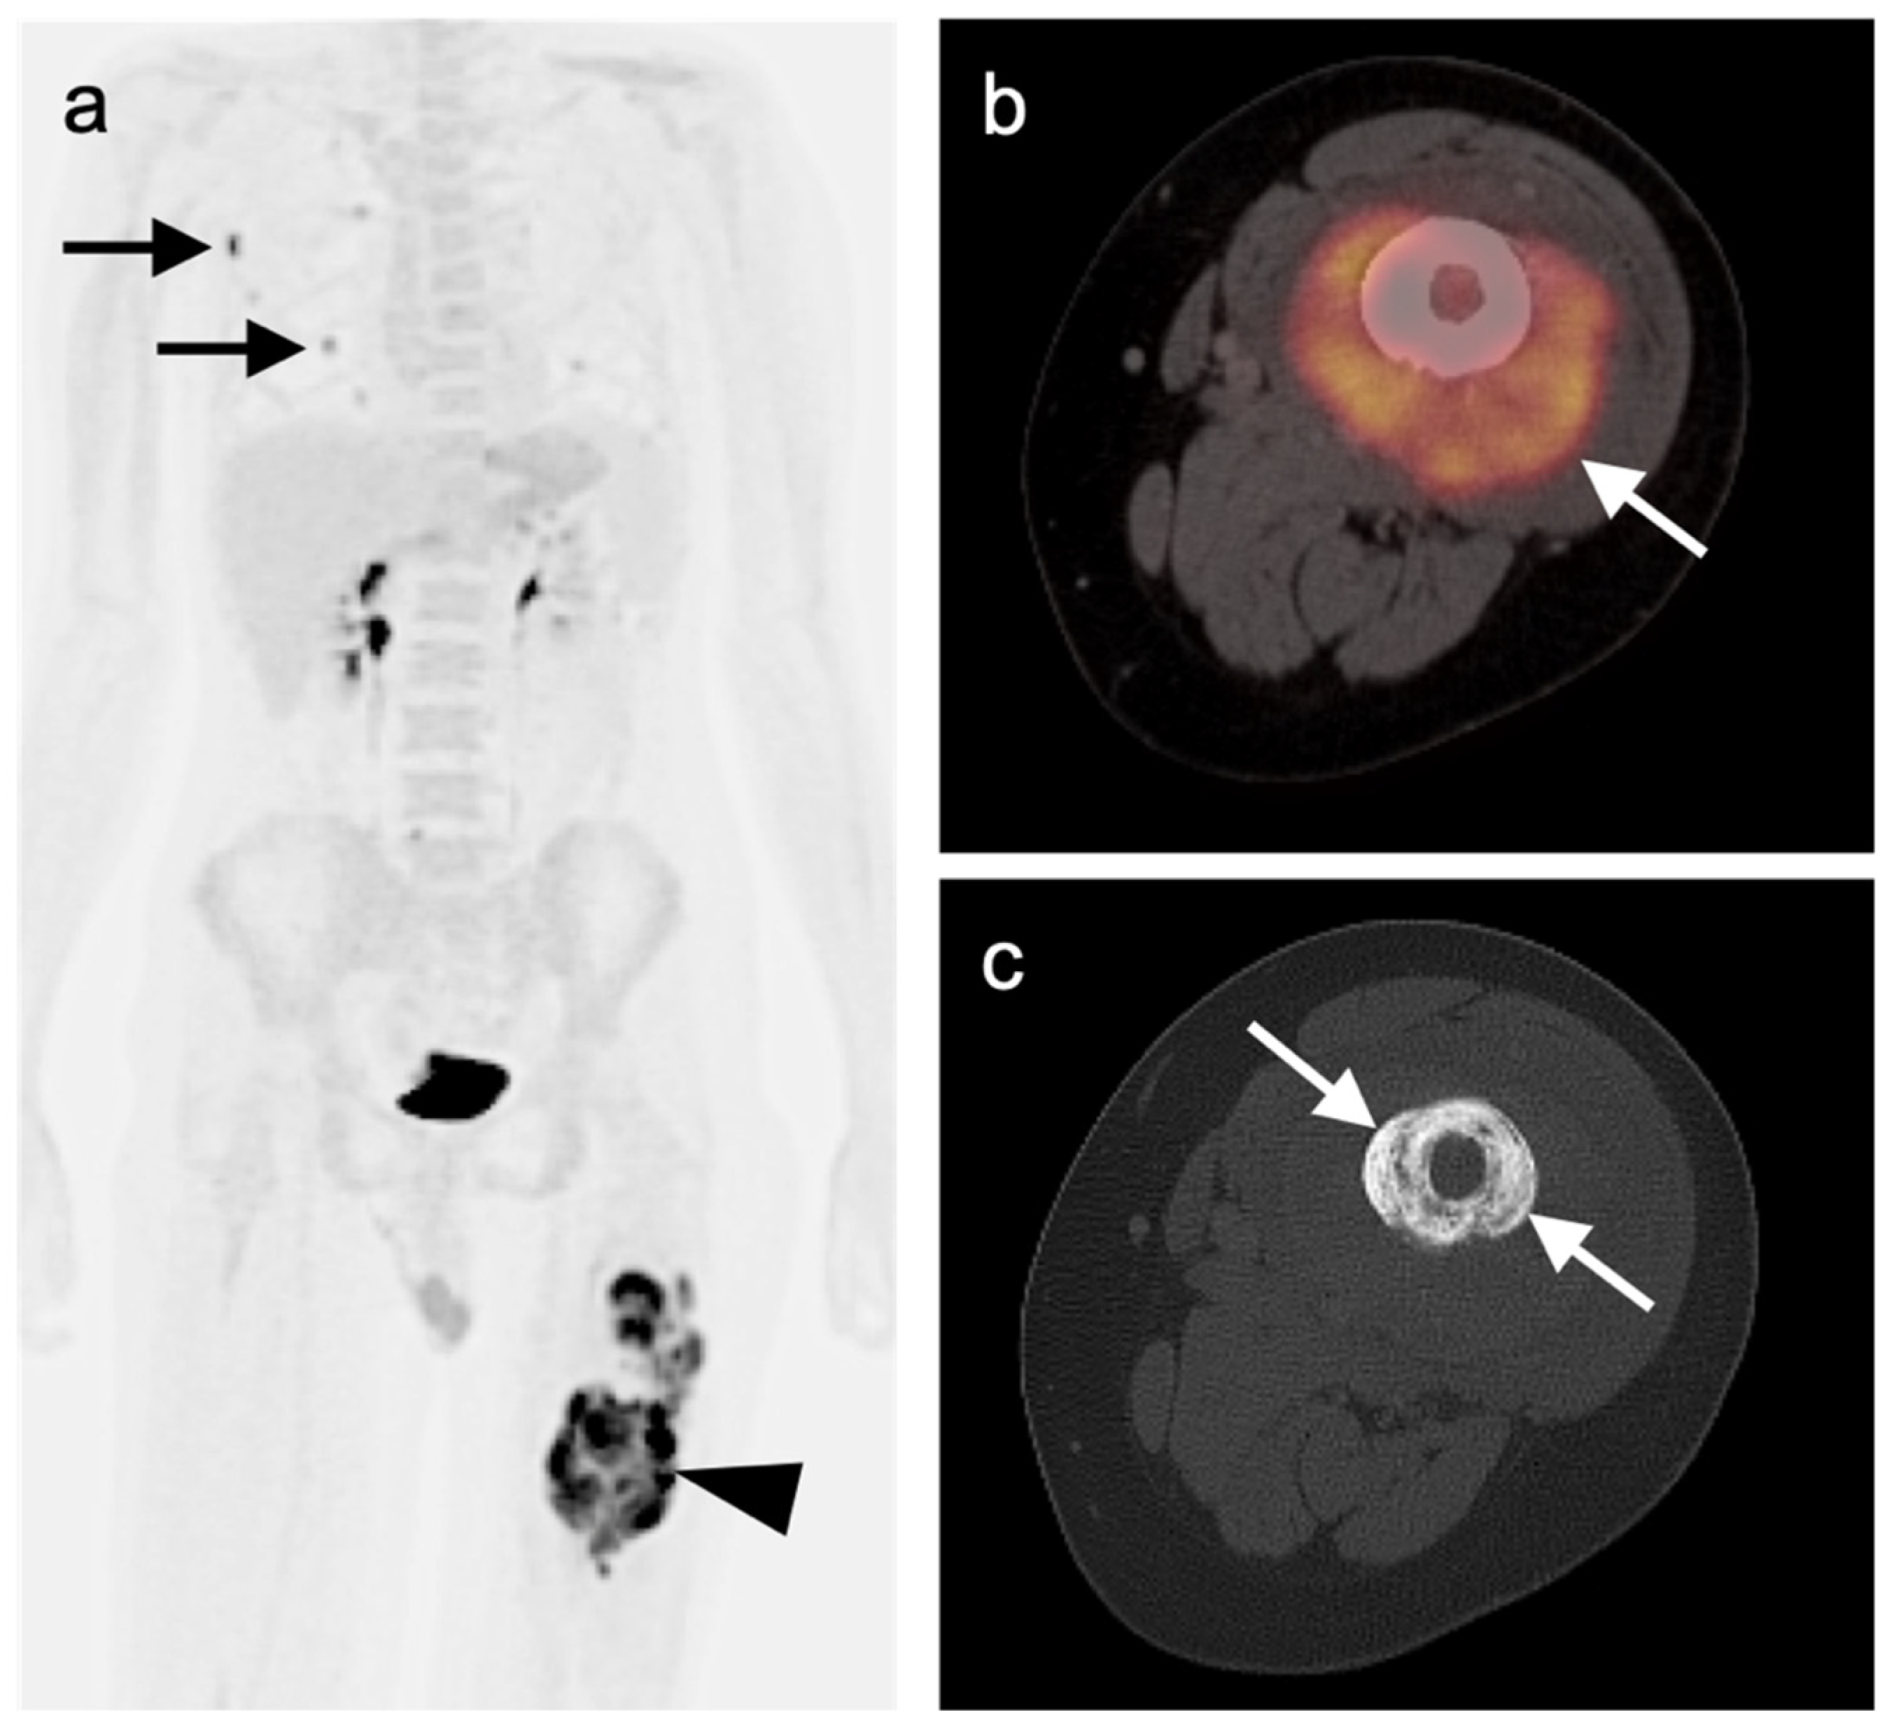

- Gao, Y.-J.; Yang, Z.; Yu, J.-Y.; Li, N.; Wang, X.-J.; Zhou, N.-N. Potential application value of PET/computed tomography in retroperitoneal leiomyosarcoma and a literature review. Nucl. Med. Commun. 2021, 42, 800–810. [Google Scholar] [CrossRef]

- Subramaniam, S.; Callahan, J.; Bressel, M.; Hofman, M.S.; Mitchell, C.; Hendry, S.; Vissers, F.L.; Van der Hiel, B.; Patel, D.; Van Houdt, W.J.; et al. The role of 18 F-FDG PET/CT in retroperitoneal sarcomas—A multicenter retrospective study. J. Surg. Oncol. 2021, 123, 1081–1087. [Google Scholar] [CrossRef]